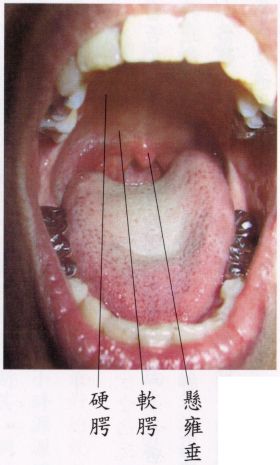

当舌尖顶‘上门牙后约一、二公分处’,‘舌面’和‘软齶’保持距离(部位见下面图示),而放松时,立即会觉得‘悬雍垂’(俗称喉咙钟)后方之咽喉,通风清凉,呼吸道有如‘拓宽’而出入息通畅。越放松、越能感受呼吸时顶上清凉,不昏沉。

┌前—硬齶:与骨相贴之硬部。上齶

上齶│

└后—软齶:悬空之软部。

(中有‘悬雍垂’)